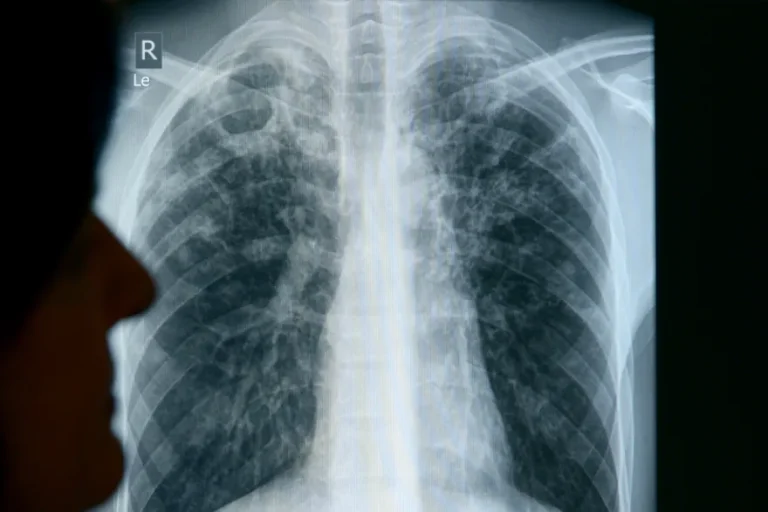

A histoplazmózis egy gombás eredetű tüdőfertőzés, amelyet a Histoplasma capsulatum nevű gomba okoz. A kórokozó a talajban él, különösen olyan helyeken, ahol:

A tünetek nagyon változatosak lehetnek – a teljes tünetmentességtől a súlyos, kórházi kezelést igénylő állapotig terjed a skála. Gyakori panaszok:

- száraz köhögés,

- mellkasi fájdalom vagy feszítés,

- nehézlégzés, véres köpet,